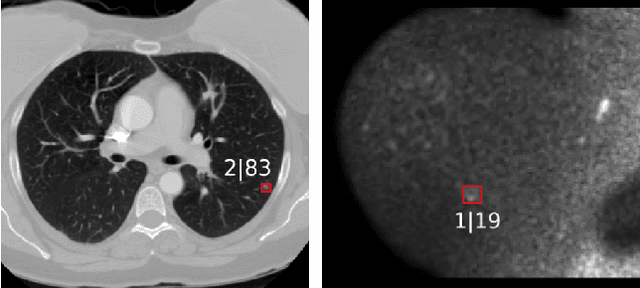

Abstract:The task of localizing and categorizing objects in medical images often remains formulated as a semantic segmentation problem. This approach, however, only indirectly solves the coarse localization task by predicting pixel-level scores, requiring ad-hoc heuristics when mapping back to object-level scores. State-of-the-art object detectors on the other hand, allow for individual object scoring in an end-to-end fashion, while ironically trading in the ability to exploit the full pixel-wise supervision signal. This can be particularly disadvantageous in the setting of medical image analysis, where data sets are notoriously small. In this paper, we propose Retina U-Net, a simple architecture, which naturally fuses the Retina Net one-stage detector with the U-Net architecture widely used for semantic segmentation in medical images. The proposed architecture recaptures discarded supervision signals by complementing object detection with an auxiliary task in the form of semantic segmentation without introducing the additional complexity of previously proposed two-stage detectors. We evaluate the importance of full segmentation supervision on two medical data sets, provide an in-depth analysis on a series of toy experiments and show how the corresponding performance gain grows in the limit of small data sets. Retina U-Net yields strong detection performance only reached by its more complex two-staged counterparts. Our framework including all methods implemented for operation on 2D and 3D images is available at github.com/pfjaeger/medicaldetectiontoolkit.